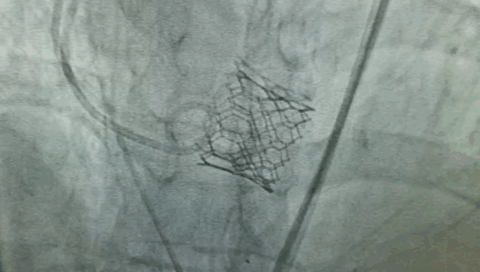

第一个病人的特点是,需要在解决主动脉瓣问题的同时,解决冠状动脉的问题。针对病人特点,来永强教授和周玉杰教授提前在网上进行了会诊,设计一站式杂交手术,前降支和右冠各放一个支架,同时用SAPIEN 3瓣膜进行TAVR手术。

“相当于经皮主动脉瓣膜植入术中同时行PCI手术,不开胸,对患者来说是获得最大的效益。”周玉杰教授表示,TAVR同期行PCI,这两个手术合在一起,带来了病人的双获益。